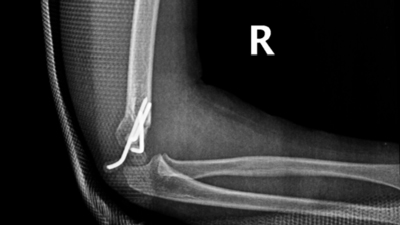

骨折部位术后

这是一种无切口、痛感小的微创治疗方法,手术过程通常不到1小时,经皮打入克氏针,骨折愈合即可取针。这种治疗方法不仅疗程相对较短,并且效果佳,不会留下大的伤疤,患处畸形发生率低。据了解,儿童骨骼与成人存在着巨大的差异,儿童处于持续生长发育的过程,除了关节骨折,大多数骨折复位到不影响正常活动即可,特别是四肢的骨折,尽量不切开复位,采取闭合复位,这样术后小朋友骨折恢复速度就会加快,且对生长发育的影响最小。